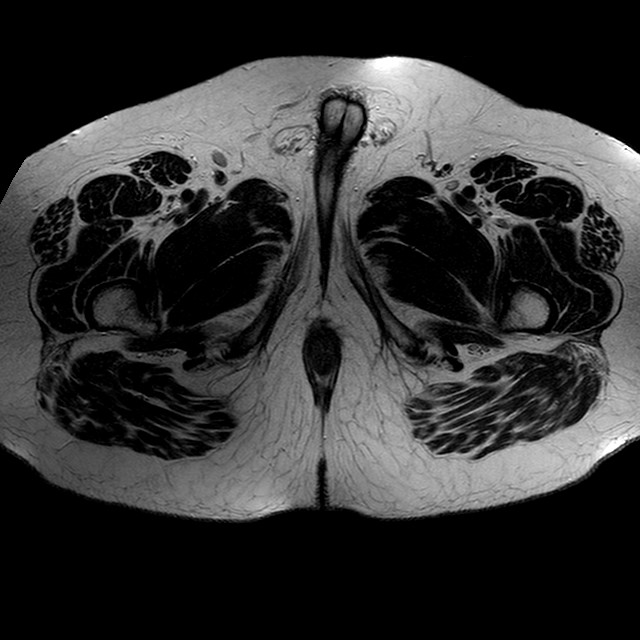

Esami: RMN BACINO

T2w TSE

Evidenti e simmetriche alterazioni osteofitosiche in regione coxo femorale con riduzione delle rime articolari. Degenerazione completa del cercine glenoideo. Non attuali segni di versamento articolare. Non segni di edema osseo che escludono attuale algodistrofia od osteonecrosi. Lieve e simmetrica riduzione del trofismo della muscolatura glutea.